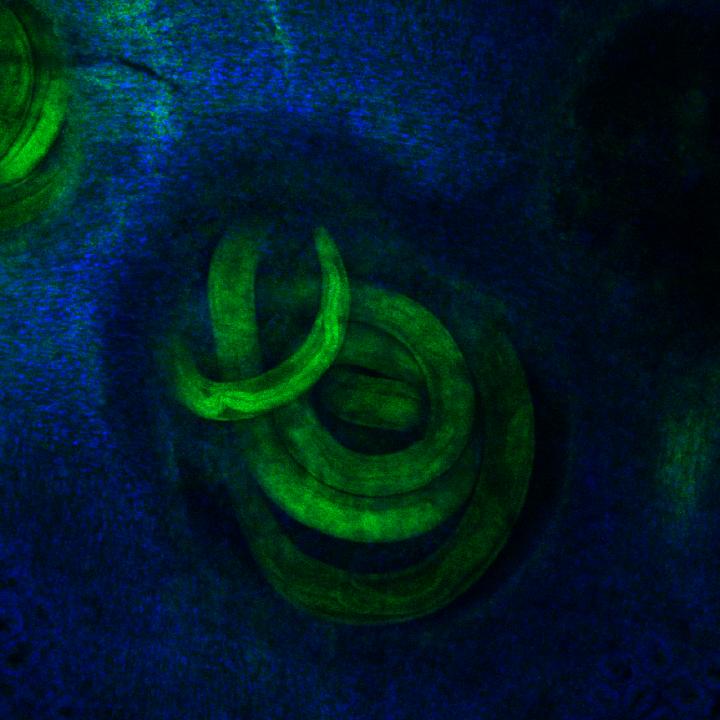

image: Larvae from the parasite Heligmosomoides polygyrus bakeri, shown here in green, develop within the intestinal tissue, with cells shown in blue.

Ferrer-Font et al. (CC BY 4.0)